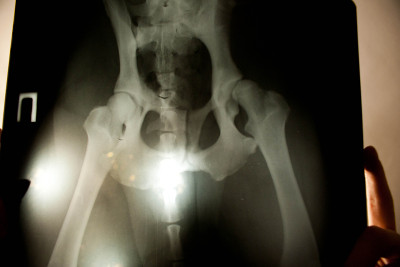

У этой собаки умеренные изменения, указывающие на дисплазию бедра с обеих сторон.

Гнезда не такие закругленные, как должны быть, а головка бедренной кости немного приплюснута.

У этой собаки дисплазия тазобедренного сустава в правом тазобедренном суставе (см. Маркер R справа)